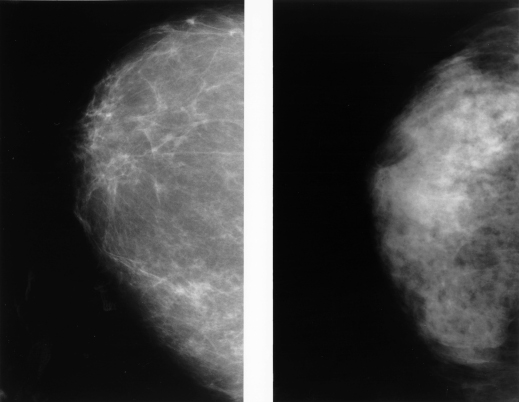

השיטה היעילה ביותר לגילוי המוקדם ביותר האפשרי של סרטן שד בנשים בריאות בנות 50 ומעלה היא ממוגרפיה, צילום רנטגן של השד. במהלך הבדיקה דוחסים את השד בין שני משטחים כדי לשטח אותו ולמנוע ממנו לזוז בעקבות תנועה של הנבדקת, דבר שיכול לפגוע באיכות הצילום. הפעלת הלחץ על השד כרוכה באי נעימות ולעתים קרובות בכאב, אך היא חשובה: שיטוח השד מקטין את הסיכוי שחלקים מרקמת השד יסתירו נגעים קטנים, ובנוסף מאפשר להפחית את כמות הקרינה הנדרשת לצילום, מאחר שעל קרני הרנטגן לעבור מרחק קצר יותר דרך השד אל הגלאי.

ממוגרפיה פחות יעילה אצל נשים עם מבנה שד צפוף, כלומר שד שמכיל מעט רקמת שומן. מבנה זה נפוץ במיוחד אצל נשים צעירות מתחת לגיל 40. רקמת השד הצפופה מקשה על פענוח תוצאות הבדיקה ומגדילה את הסיכון לתשובה שלילית כוזבת. כלומר, היא עלולה להסוות גידולים קיימים ולכן להוביל לקבלת תוצאות תקינות אף כשיש בשד גוש סרטני.

בגלל הרקמה הצפופה עלולות להתקבל גם יותר תוצאות חיוביות כוזבות, כלומר הופעת ממצאים שחשודים כסרטניים אך שאינם באמת כאלה. תשובה חיובית כוזבת מעוררת חששות מיותרים, ואף עלולה להוביל לבדיקות נוספות, כדי לשלול קיומו של סרטן. חלק מהבדיקות האלו הן פולשניות, כמו נטילת דגימת רקמה (ביופסיה) או ניתוחים. הסיכוי הכולל של אישה שנבדקת פעם בשנתיים לקבל תוצאה חיובית כוזבת אחת, בתקופה של 10 שנים, הוא 38 אחוז. עם זאת, הסיכוי שאישה תצטרך לעבור ביופסיה בגלל תוצאה חיובית כוזבת, ולא תוכל להסתפק רק בבדיקות דימות חוזרות, הוא פחות משבעה אחוזים.